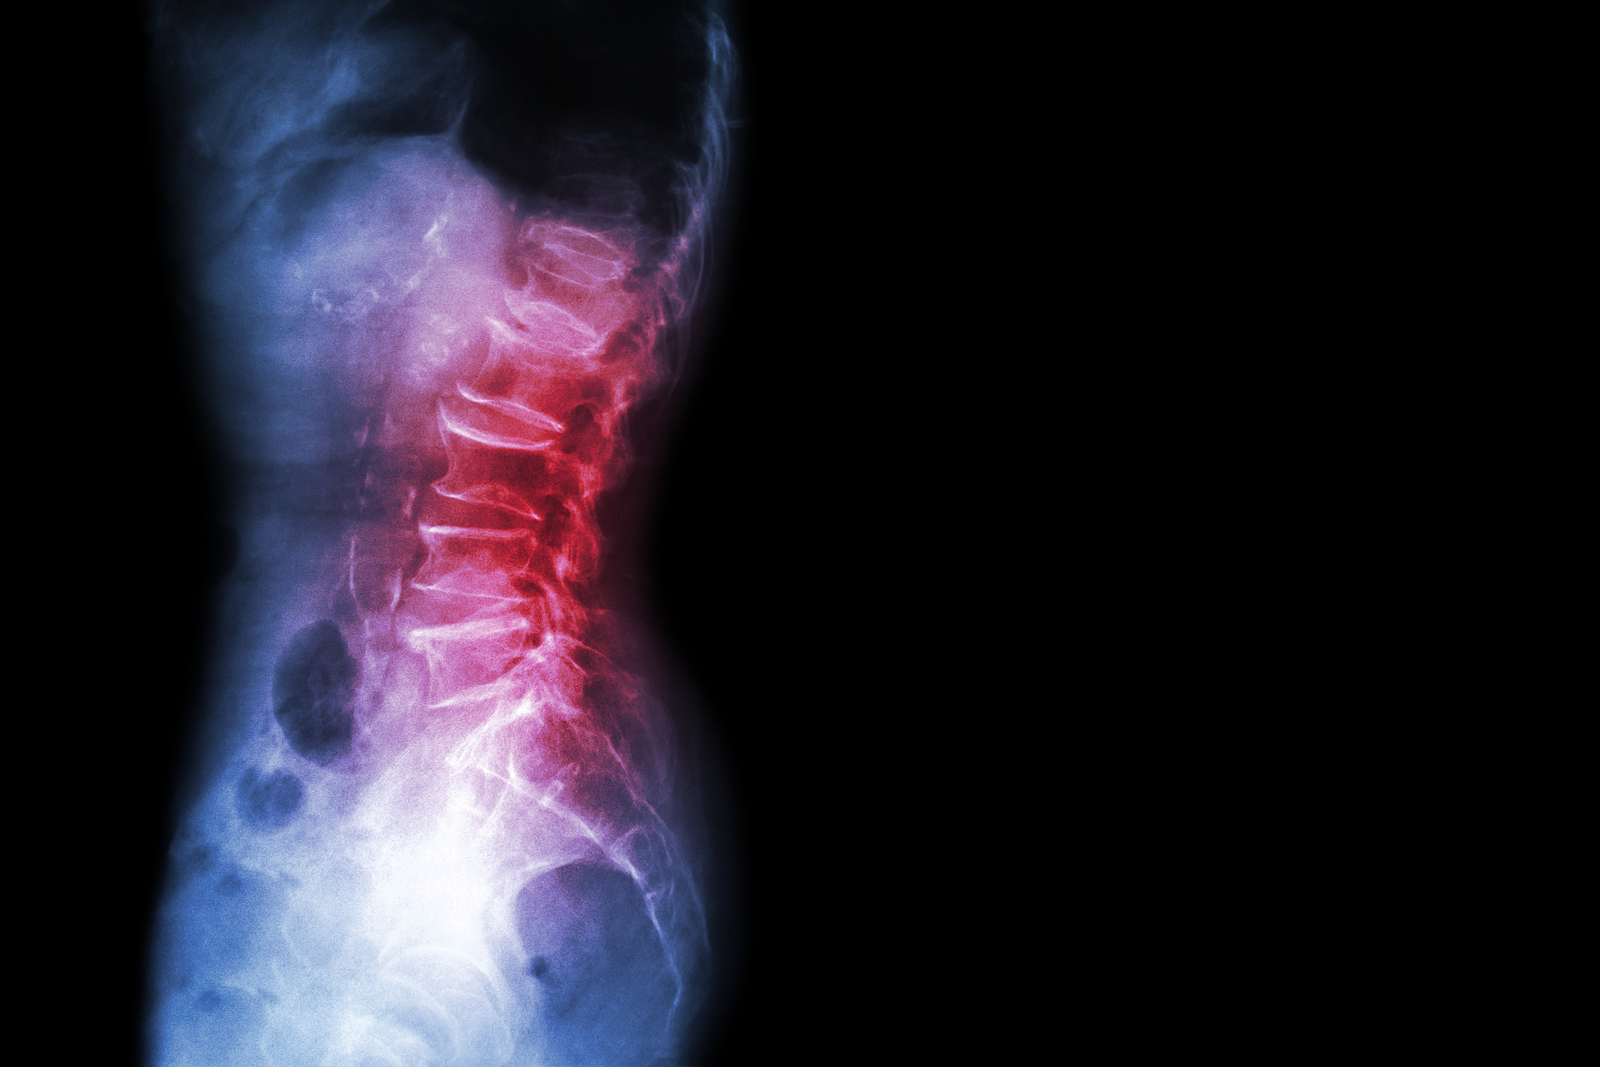

Anatomy

What Makes Up the Lumbar Spine?

The human spine is made up of 24 spinal bones, called vertebrae, as well as the sacrum and the coccyx. The sacrum is a triangular bone near the bottom of the spine and the coccyx is more commonly known as the tailbone.

Vertebrae are stacked on top of one another to create the spinal column. The spinal column gives the body its form and helps sustain an upright position.

The lumbar spine—where pain is often experienced—is made up of five vertebrae positioned near the bottom of the spinal column. Doctors often refer to these vertebrae as levels L1, L2, L3, L4 and L5. The ‘L’ refers to ‘lumbar’. The lowest vertebra, L5, is connected to the top of the sacrum—a triangular bone at the base of the spine that is located between the two pelvic bones. Some people are born with an extra or sixth lumbar vertebra called L6. Having an extra vertebra doesn't usually cause physical problems.

The main portion of a vertebra is a circular segment of bone called a vertebral body. This structure supports about 80% of the body's weight load while an individual is standing. Vertebral bodies are also the point of contact or attachment for the spinal discs located between vertebrae. The lumbar vertebral bodies are taller and bulkier than the vertebrae in the cervical and thoracic regions because the lower back is designed to withstand more pressure and weight during daily activities such as lifting, carrying, and twisting. The bulkier vertebral bodies also provide support that allows the large, powerful muscles attached to or near the lumbar spine to work effectively.

The second portion of the vertebra is a body protrusion called the spinous process. This is that hard bony structure you feel when you run your fingers down the back of your spine. The vertebral body and the spinous process are joined together by vertebral arches. The arches form a ring that enclose the spinal cord and cerebrospinal fluid. Vertebrae are also connected by fibrous facet joints that are located on each side of the spine. The joints improve the stability and flexibility of the spine. The stacked formation of vertebrae along the spinal column forms a long, hollow tube that protects the spinal cord.

X-rays are usually the first test ordered before any of the more specialized tests are completed. X-rays use electromagnetic radiation to show problems with bones and can also reveal problems such as fractures, infections, or bone tumors. X-rays of the spine can give your doctor information about bone alignment and can demonstrate how much degeneration has occurred in the spine. Both alignment and degeneration can affect the amount of space in the neural foramina and between the discs, which subsequently impacts the nerves in the area. This is important information your health care professional can use to establish a treatment plan.